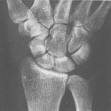

手舟骨手舟骨(Scaphoidbone),又稱腕舟狀骨,古稱高骨、龍骨,屬於腕骨(carpalbones),是近排腕骨中最長最大的一塊,呈長弧形,其狀如舟,很不規則,其遠端超過近排腕骨,平頭狀骨的腰部,其腰部相當於兩排腕間骨關節面的平面。

腕舟狀骨分為結節、腰部和體部三部分。

舟狀骨周圍有5個關節面,表面大多部分均由關節軟骨覆蓋。

1)遠端呈凹面與頭狀骨構成關節;

2)近端呈凸面與橈骨遠端構成關節;

3)尺側與月骨構成關節;

4)橈側與大、小多角骨分別構成關節。(2個)

腕舟狀骨骨折是較常見的骨折,占腕骨骨折約71.2%,多發於青壯年。